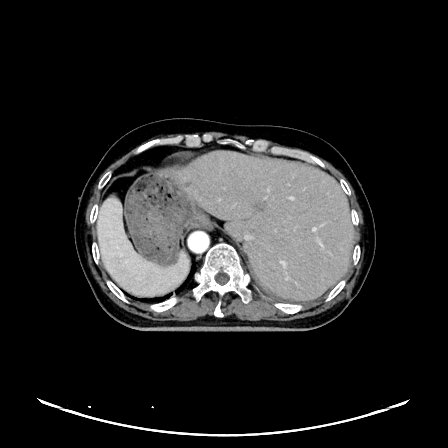

Qualitative evaluation.

To provide a more intuitive observation of our medical vision generalist, we provide the visualization of different tasks in Figure 4.